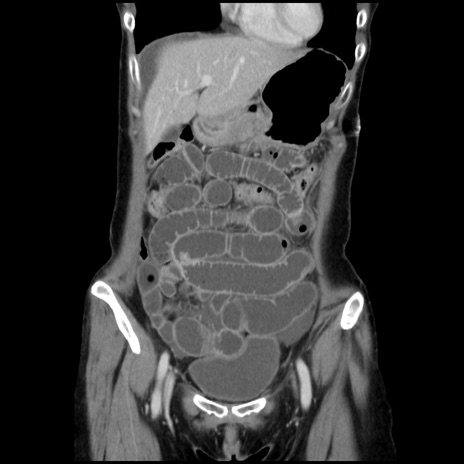

症例32(冠状断像)

【症例】40歳代 女性

【主訴】上腹部痛、嘔気・嘔吐

【現病歴】約9時間前頃から急に上腹部痛、嘔気、嘔吐が出現。改善しないため救急要請。

【既往歴】子宮頚癌(広汎子宮全摘術、放射線療法)、腸閉塞

【身体所見】腹部:平坦、軟、腸雑音亢進、上腹部を中心に腹部全体に圧痛あり。

【データ】WBC 8400、CRP 0.03